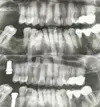

Uzmanlık alanları

Diş hekim